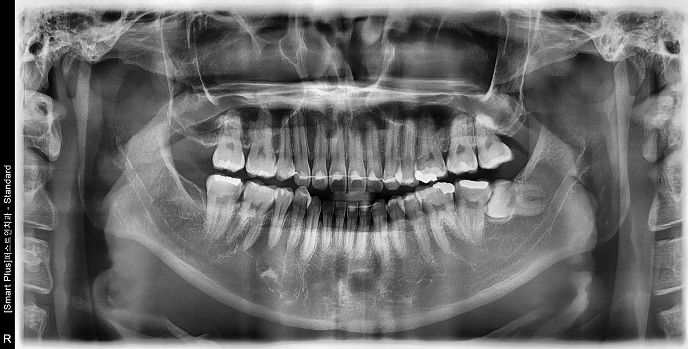

• STEP 02 X-ray 확인

뿌리 형태와 위치, 신경·상악동과의 거리를 파악해 안전한 발치 계획을 세웁니다.

• 20대 남성 | #38 사랑니발치 | 치료기간 당일

Before 2022.06.24

After 2022.06.24

• 30대 여성 | #38 사랑니발치 | 치료기간 당일

Before 2025.03.06

After 2025.03.06